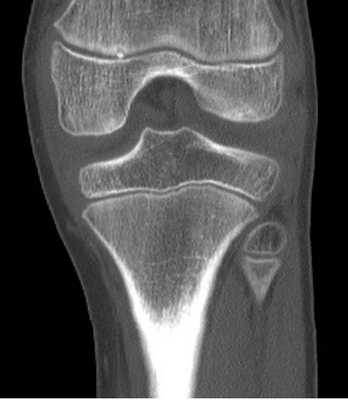

МСКТ коленного сустава (коронарная проекция)

Стандартные проекции, применяемые при рентгенографии коленного сустава - прямая (передне-задняя) и боковая (рис.1). По мере необходимости их дополняют правой или левой косой, а также аксиальной проекциями. Основным правилом при рентгенологическом исследовании коленного сустава является полипозиционность.

Эффективность рентгенодиагностики повреждений коленного сустава напрямик зависит от качества рентгенограмм, критериями которого являются:

- в прямой проекции:

- симметричность аксиальных сторон обоих мыщелков бедренной кости;

- расположение межмыщелковых возвышений по центру межмыщелковой ямки;

- частичная маскировка головки малоберцовой кости метаэпифизом большеберцовой кости (примерно на 1/3 своего поперечного размера);

- наложение контуров надколенника на центральную область метаэпифиза бедренной кости;

- в боковой проекции:

- возможность просмотра надколенно-бедренного сустава и бугристости большеберцовой кости.